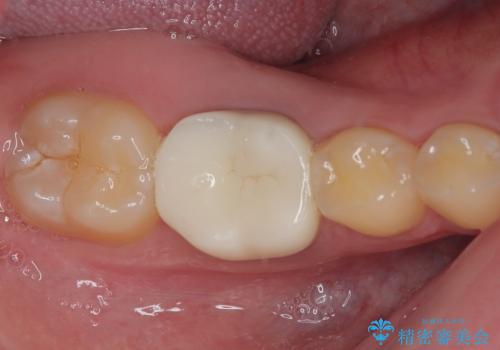

見た目、噛み合わせともに満足していただけました。

歯質と被せ物(クラウン)の境目も適合の良いものができました。